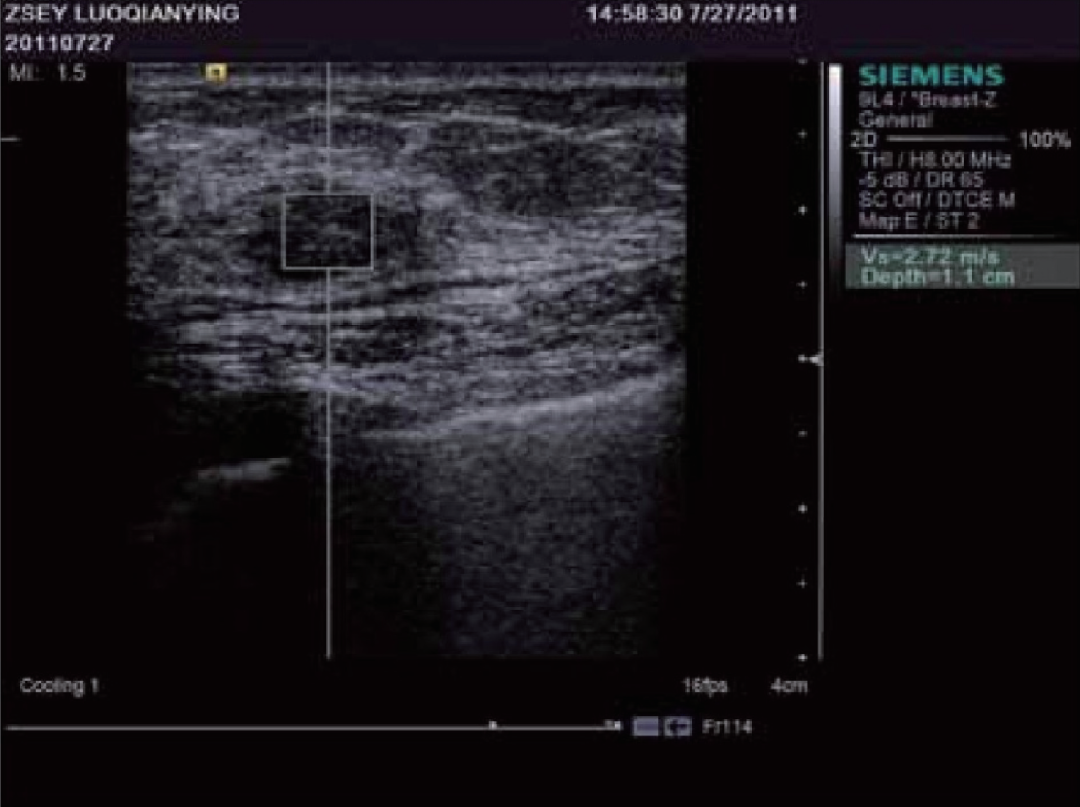

谐波运动成像最早由Maleke等人提出。通过探头产生的超声波对组织施加周期性的声辐射力,使组织产生谐波运动。 通过获取组织被激发前后的B超图像并对其进行运动估计,可以间接反映组织的弹性状况。该方法可以准确反映深部组织的局部弹性状况,但由于需要在激发信号的同时监测组织的运动,因而采集到的B超信号容易受到激发信号的严重干扰,这是该成像方法迄今为止尚未得到完美解决的主要问题。当声辐射力作用在组织上时会激发出剪切波,剪切波弹性成像正是通过检测这一剪切波的传播来达到成像的目的,最早由美国学者Sarvazyan和Emelianov提出。他们利用高强度聚焦超声探头产生声辐射力,在人体组织中产生了明显的剪切波,并运用磁共振成像方法监测该剪切波的传播情况。由于剪切波速与人体组织的粘弹特性紧密相关,因此通过检测剪切波的传播速度等参数可以获取组织的弹性信息。图12显示了某一慢性肝病患者的肝脏弹性成像图。声辐射力脉冲成像技术最早由杜克大学的学者Nightingale等人提出,该方法通过高能聚焦超声探头在局部组织中产生短暂的高强度声辐射力,从而推动组织产生一定的应变,再通过追踪这些微小应变和剪切波的传播来判断组织的粘弹特性。研究人员发现,组织对于脉冲声辐射力的瞬态响应直接相关于局部区域的硬度大小,而通过求解亥姆霍兹方程的反问题方法可以量化组织中剪切波的波速。Nightingale等通过详细的数值仿真和体模研究证实了声辐射力脉冲成像的可行性,并得到了与传统B超图像相比更高的对比度和分辨力。如今的声辐射力脉冲成像已在临床上具备多种脏器检查的能力,图13显示了某位良性纤维瘤患者的乳腺声辐射力脉冲成像图。

图13 乳腺良性纤维瘤患者的声辐射力脉冲成像图